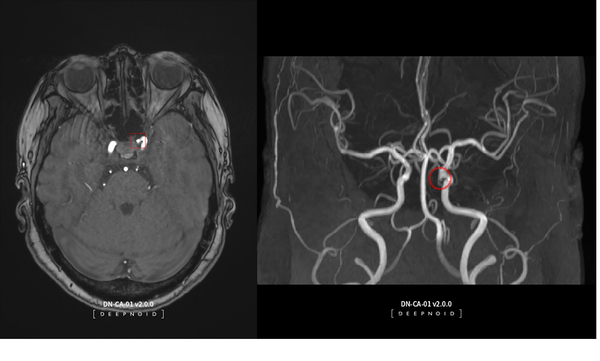

조정현 하나증권 연구원은 "딥노이드는 2008년 설립된 국내 1세대 AI 개발 전문 업체로, 사업군은 크게 의료 AI와 산업 AI로 분류된다"며 "뇌동맥류 AI 영상 판독 솔루션인 딥뉴로(DEEP:NEURO)와 딥러닝 기반 머신비전 솔루션인 딥팩토리(DEEP:FACTORY)를 주력 제품으로 보유하고 있다"고 소개했다.

이어 "딥노이드는 딥뉴로의 비급여 적용을 통한 의료 AI 매출 본격화에 따라 내년부터 폭발적인 성장이 예상된다"며 "연내 딥팩토리의 글로벌 톱티어(top-tier) 2차전지 신규 고객사 향 수주 확대에 따라 2차전지 시장 가치가 더해질 것"이라고 기대했다.